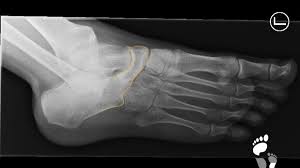

Den gesamten Komplex bilden außerdem Gelenke Fußwurzelgelenke Gelenke der Mittelfußknochen und Zehengelenke viele für die. Eine weitere Ursache für Schmerzen an der Fußaußenseite ist die Fraktur des fünften Mittelfußknochens. Der menschliche Fuß besteht aus 26 Knochen.

Fußknochen an der seite. Nachdem der erste Anlauf ein Eltern- Lehrerinnen- Team auf die Beine zu stellen im vergangenen Jahr an körperlichen Gebrechen gebrochener Fußknochen gescheitert war starteten wir in diesem Jahr einen neuen Versuch lauffreudige Menschen für den Hanauer Stadtlauf zu begeistern. Der Fuß besteht aus Fußwurzelknochen Mittelfuß und den fünf Zehen auch Vorfuß genannt. Der Fuss ist an der Stelle mit dem Körper verbunden wo Knochen des Rückfusses auf das Schien- und Wadenbein treffen Knöchel.

Andere Erkrankungen der Füße entstehen durch Krankheiten die viele Bereiche des Körpers betreffen wie Diabetes mellitus Gicht oder andere Arthritisformen. Die Knochen des Fußskeletts werden durch zahlreiche Bänder zusammengehalten und sind durch Gelenke miteinander verbunden. Alle von diesen Cookies erfassten Informationen werden aggregiert und sind deshalb anonym.